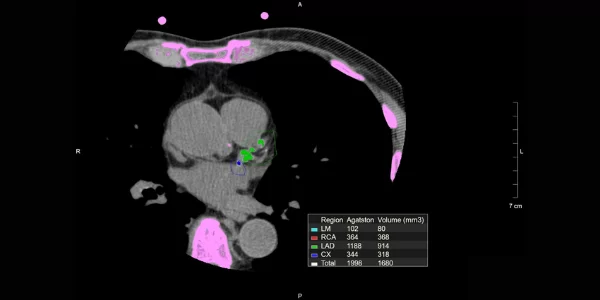

O Escore de Cálcio Coronário é obtido por meio de uma tomografia computadorizada (TC) que detecta depósitos de cálcio nas artérias coronárias. O cálcio se acumula nas paredes das artérias como parte do processo de aterosclerose, uma condição onde as artérias ficam endurecidas e estreitas devido à formação de placas. O exame mede a quantidade total de cálcio nas artérias coronárias e fornece um escore que ajuda a estimar o risco de eventos cardíacos futuros.

- Imagens e Cálculo do Escore: O equipamento calcula o escore de cálcio com base na quantidade de cálcio detectada nas artérias coronárias. O escore é um número que reflete a carga total de cálcio, indicando o nível de aterosclerose presente.

- Análise dos Resultados: Os resultados são interpretados por um radiologista, que fornece um relatório detalhado com o escore de cálcio e sua interpretação em relação ao risco cardiovascular.